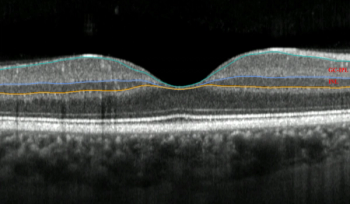

Researchers indicated OCT can be vital to a timely diagnosis and treatment for scleritic patients.